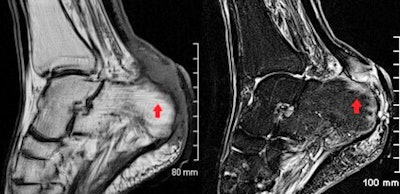

"MRI provides the most accurate evaluation of the extent of deeper infections and of surrounding soft tissue anatomy and can also assess for associated abnormality of adjacent bones or joints," they wrote. "On MRI, soft tissue abscesses demonstrate internal high T2 and STIR signal with corresponding low T1 signal, peripherally enhancement following intravenous gadolinium administration and restrict diffusion on DWI."

MRI protocols for suspected bone and joint complications of injected drug use should include a fluid-sensitive sequence such as STIR, in addition to T2 or proton density and T1-weighted sequences in at least two planes. Bone marrow edema is the earliest imaging finding identifiable in acute osteomyelitis and appears on MRI as high T2 and STIR signal intensity of the bone with corresponding low T1 signal. Enhancement following contrast administration is also seen.

High T2/STIR signal without low T1 signal is less specific and may represent reactive osteitis rather than osteomyelitis. Cortical bone destruction can be identified as loss of the normal peripheral T1 hypointense cortical rim. Assessment of the extent of the infection in adjacent soft tissues, differentiation of bone from soft tissue infection and surgical planning can also be reliably achieved on MRI, according to the authors.